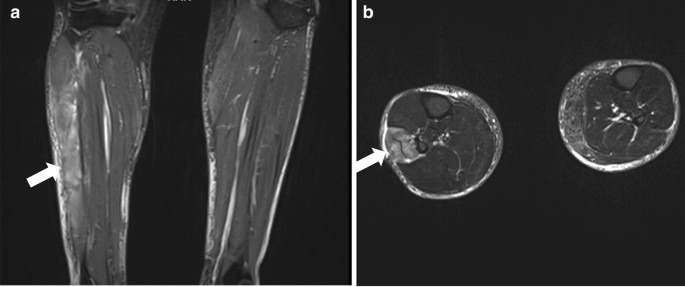

Bedside venous blood gas analysis revealed a normal pH of 7.4 and a normal electrolyte profile, with blood glucose of 5.8 mmol/L (normal reference = 7–11.1). The serum lactate level was 1.6 mmol/L (normal < 1.8). Whole blood analysis revealed hemoglobin of 155 g/L (normal reference = 130–180), with a total white blood cell count of 9.9 × 109/L (normal reference = 3.7–11) and a normal differential count. Platelet count was 275 × 109/L (normal reference = 150–450). Renal and liver function and coagulation parameters were all normal. C-reactive protein was 4.3 mg/L (normal reference = < 5) and the D-dimer level was normal at 327 µg/L (normal reference = 0–500). Considering the clinical context and near normal biochemical parameters, the initial working clinical suspicion was compartment syndrome of the right leg despite the absence of an obvious etiology. This was based on the classical presentation, especially when D-dimers were negative, making deep vein thrombosis unlikely. Urgent magnetic resonance imaging of the lower limbs was done, which revealed gross edema and swelling of the right lateral leg compartment involving the peroneus and longus muscle, consistent with acute lateral compartment syndrome (Fig 1).

Contrast-enhanced magnetic resonance imaging of both lower legs: a coronal cut and b axial cuts. Both demonstrate (indicated by a white arrow) right-sided gross edema and swelling of the lateral lower leg compartment involving the peroneus brevis and longus muscles, consistent with acute lateral compartment syndrome. No intramuscular hemorrhage is evident. There is extensive soft tissue edema. Normal appearance of the anterior, deep and superficial compartments. Diagnosis favors acute lateral compartment syndrome of the right leg